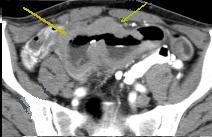

| Adeno carcinoma duodenum :

Epaissisement de la paroie duodenum en

circonferentielle , infiltrant et irreguliairement .

Image de stenose de la lumiere du portion lesionaire

. Image TDM en coupe axilae . |

Mema cas ( fleche

rouge ) en coupe cornale ( frontal )